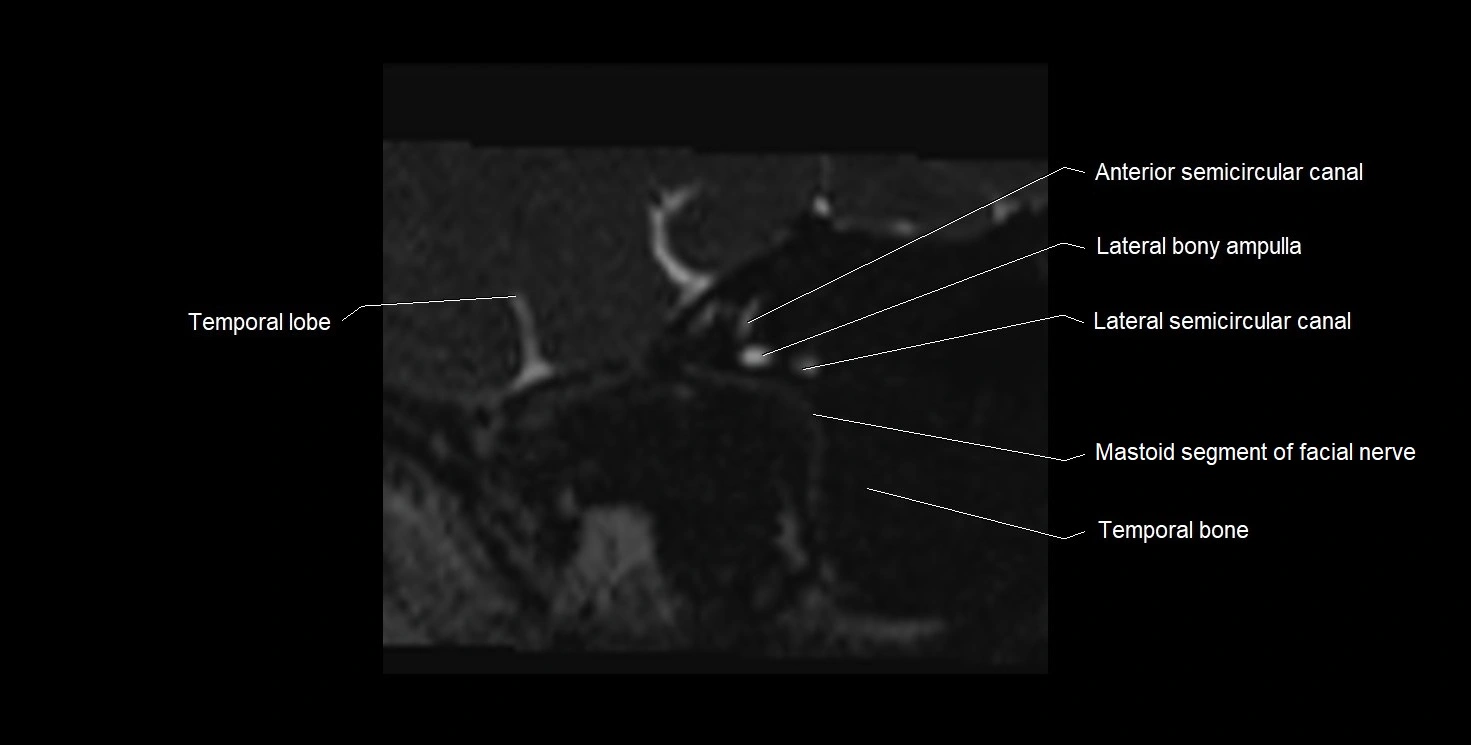

MRI Appearance

• The abducens nerve is a small, thin, linear structure

• Best visualized on high-resolution T2-weighted 3D MRI sequences (e.g., FIESTA or CISS)

• Seen as a hypointense (dark) line running from the brainstem at the pontomedullary junction, traversing the prepontine cistern, and entering Dorello’s canal under the petrosphenoidal ligament, then into the cavernous sinus, and finally the orbit

• May be challenging to visualize in standard MRI due to its small size

• Pathology may be inferred by absence, displacement, or enhancement of the nerve